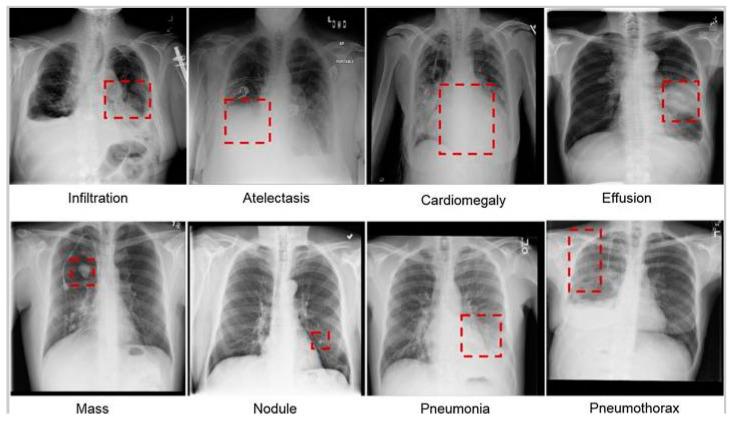

Our research focused on creating an advanced machine-learning algorithm that accurately detects anomalies in chest X-ray images to provide healthcare professionals with a reliable tool for diagnosing various lung conditions. To achieve this, we analysed a vast collection of X-ray images and utilised sophisticated visual analysis techniques; such as deep learning (DL) algorithms, object recognition, and categorisation models. To create our model, we used a large training dataset of chest X-rays, which provided valuable information for visualising and categorising abnormalities. We also utilised various data augmentation methods; such as scaling, rotation, and imitation; to increase the diversity of images used for training. We adopted the widely used You Only Look Once (YOLO) v8 algorithm, an object recognition paradigm that has demonstrated positive outcomes in computer vision applications, and modified it to classify X-ray images into distinct categories; such as respiratory infections, tuberculosis (TB), and lung nodules. It was particularly effective in identifying unique and crucial outcomes that may, otherwise, be difficult to detect using traditional diagnostic methods. Our findings demonstrate that healthcare practitioners can reliably use machine learning (ML) algorithms to diagnose various lung disorders with greater accuracy and efficiency.